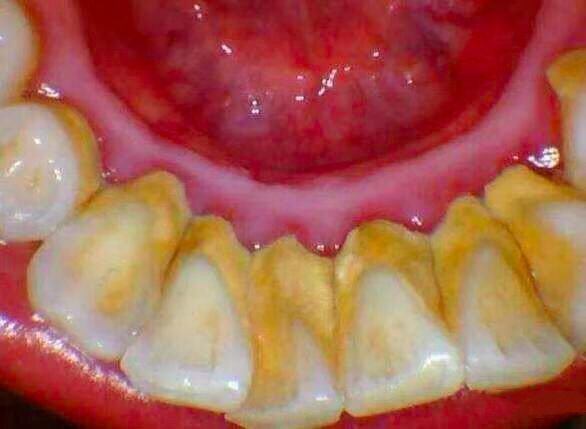

通过每天正确、高效地刷牙,可以让牙菌斑维持在不致病的水平。否则,牙菌斑堆积、钙化,将逐渐形成牙结石。

牙结石

当牙结石达到一定程度,就会刺激牙龈发炎,刷牙出血。

洗牙前后对比